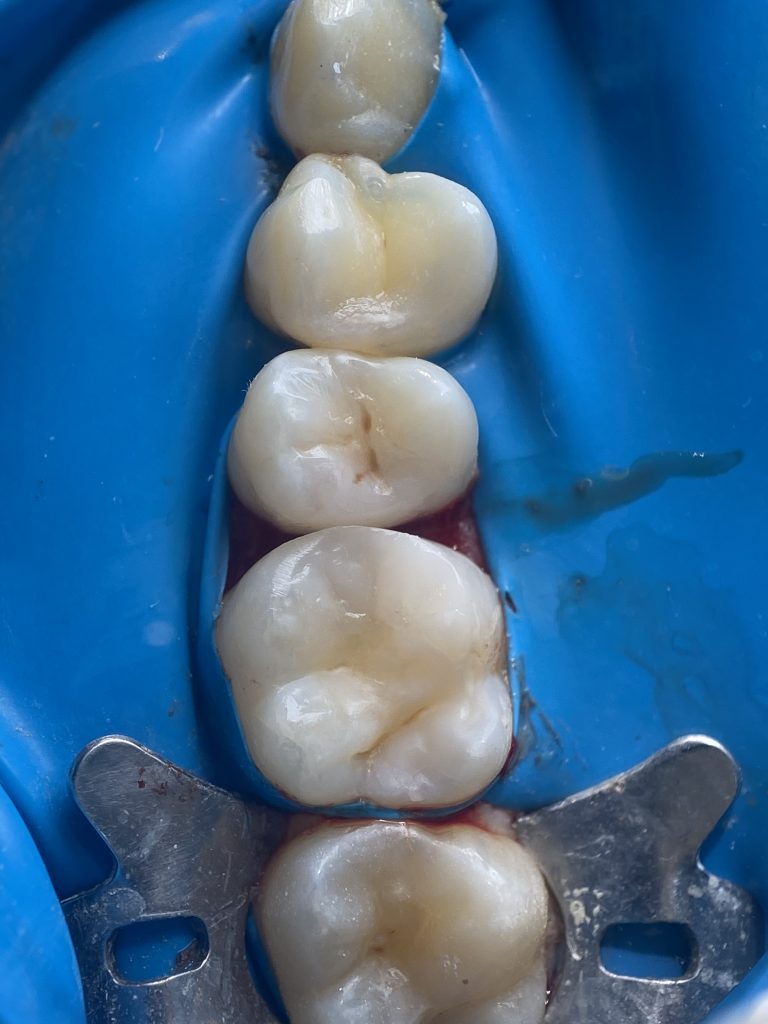

*Completion of the palatal cusp

*The cusp was completed with bulk-fill flowable composite to correctly position the matrix band and prevent the ring from deforming the band and disrupting the emergence profile.